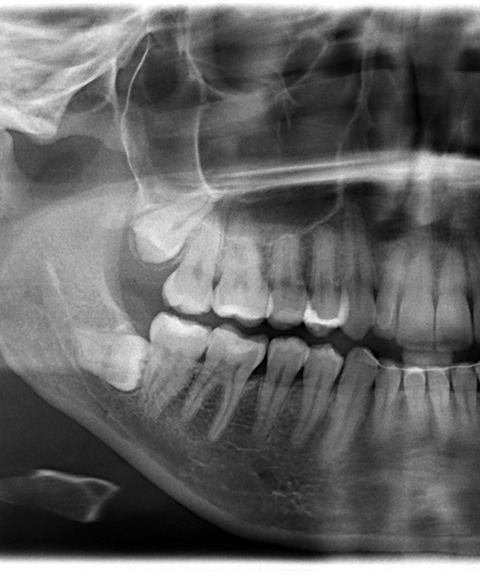

First, Dr. Ross will examine your mouth and take digital X-rays to see the exact position of your wisdom teeth. For simple extractions, these teeth are gently loosened and removed after numbing the area with local anesthesia. If you have dental anxiety, a strong gag reflex, or a resistance to anesthesia, dental sedation can also be used for comfort.

If a tooth is impacted, Dr. Ross may need to make a small incision in the gum or section the tooth into pieces for safe removal. As a trained periodontist, he has performed many of these surgical extractions with care and precision, so you’re in good hands.